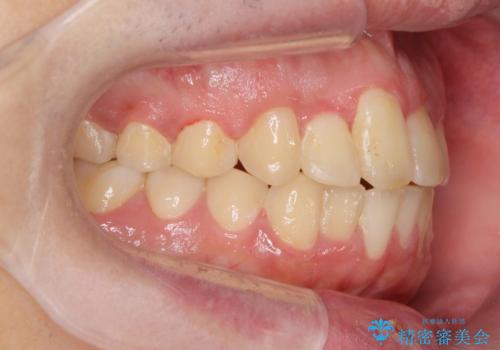

正中過剰埋伏歯で生じた前歯の審美障害 矯正治療での改善

見た目、噛み合わせが大きく改善し、大変喜んでいただくことができました。